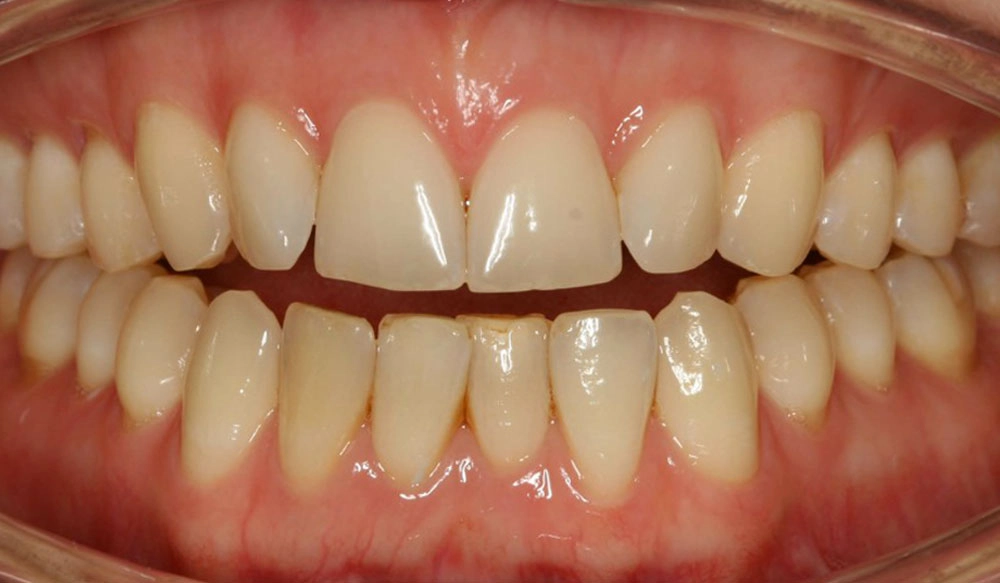

Chen chúc

Chen chúc là tình trạng có sự chênh lệch giữa kích thước răng và không gian có sẵn để sắp xếp răng trên cung răng.

Thông tin bệnh nhân:

Tuổi: 17

Giới tính: nữ

Lựa chọn điều trị Invisalign: Invisalign Comprehensive

Tổng thời gian điều trị:

29 tháng